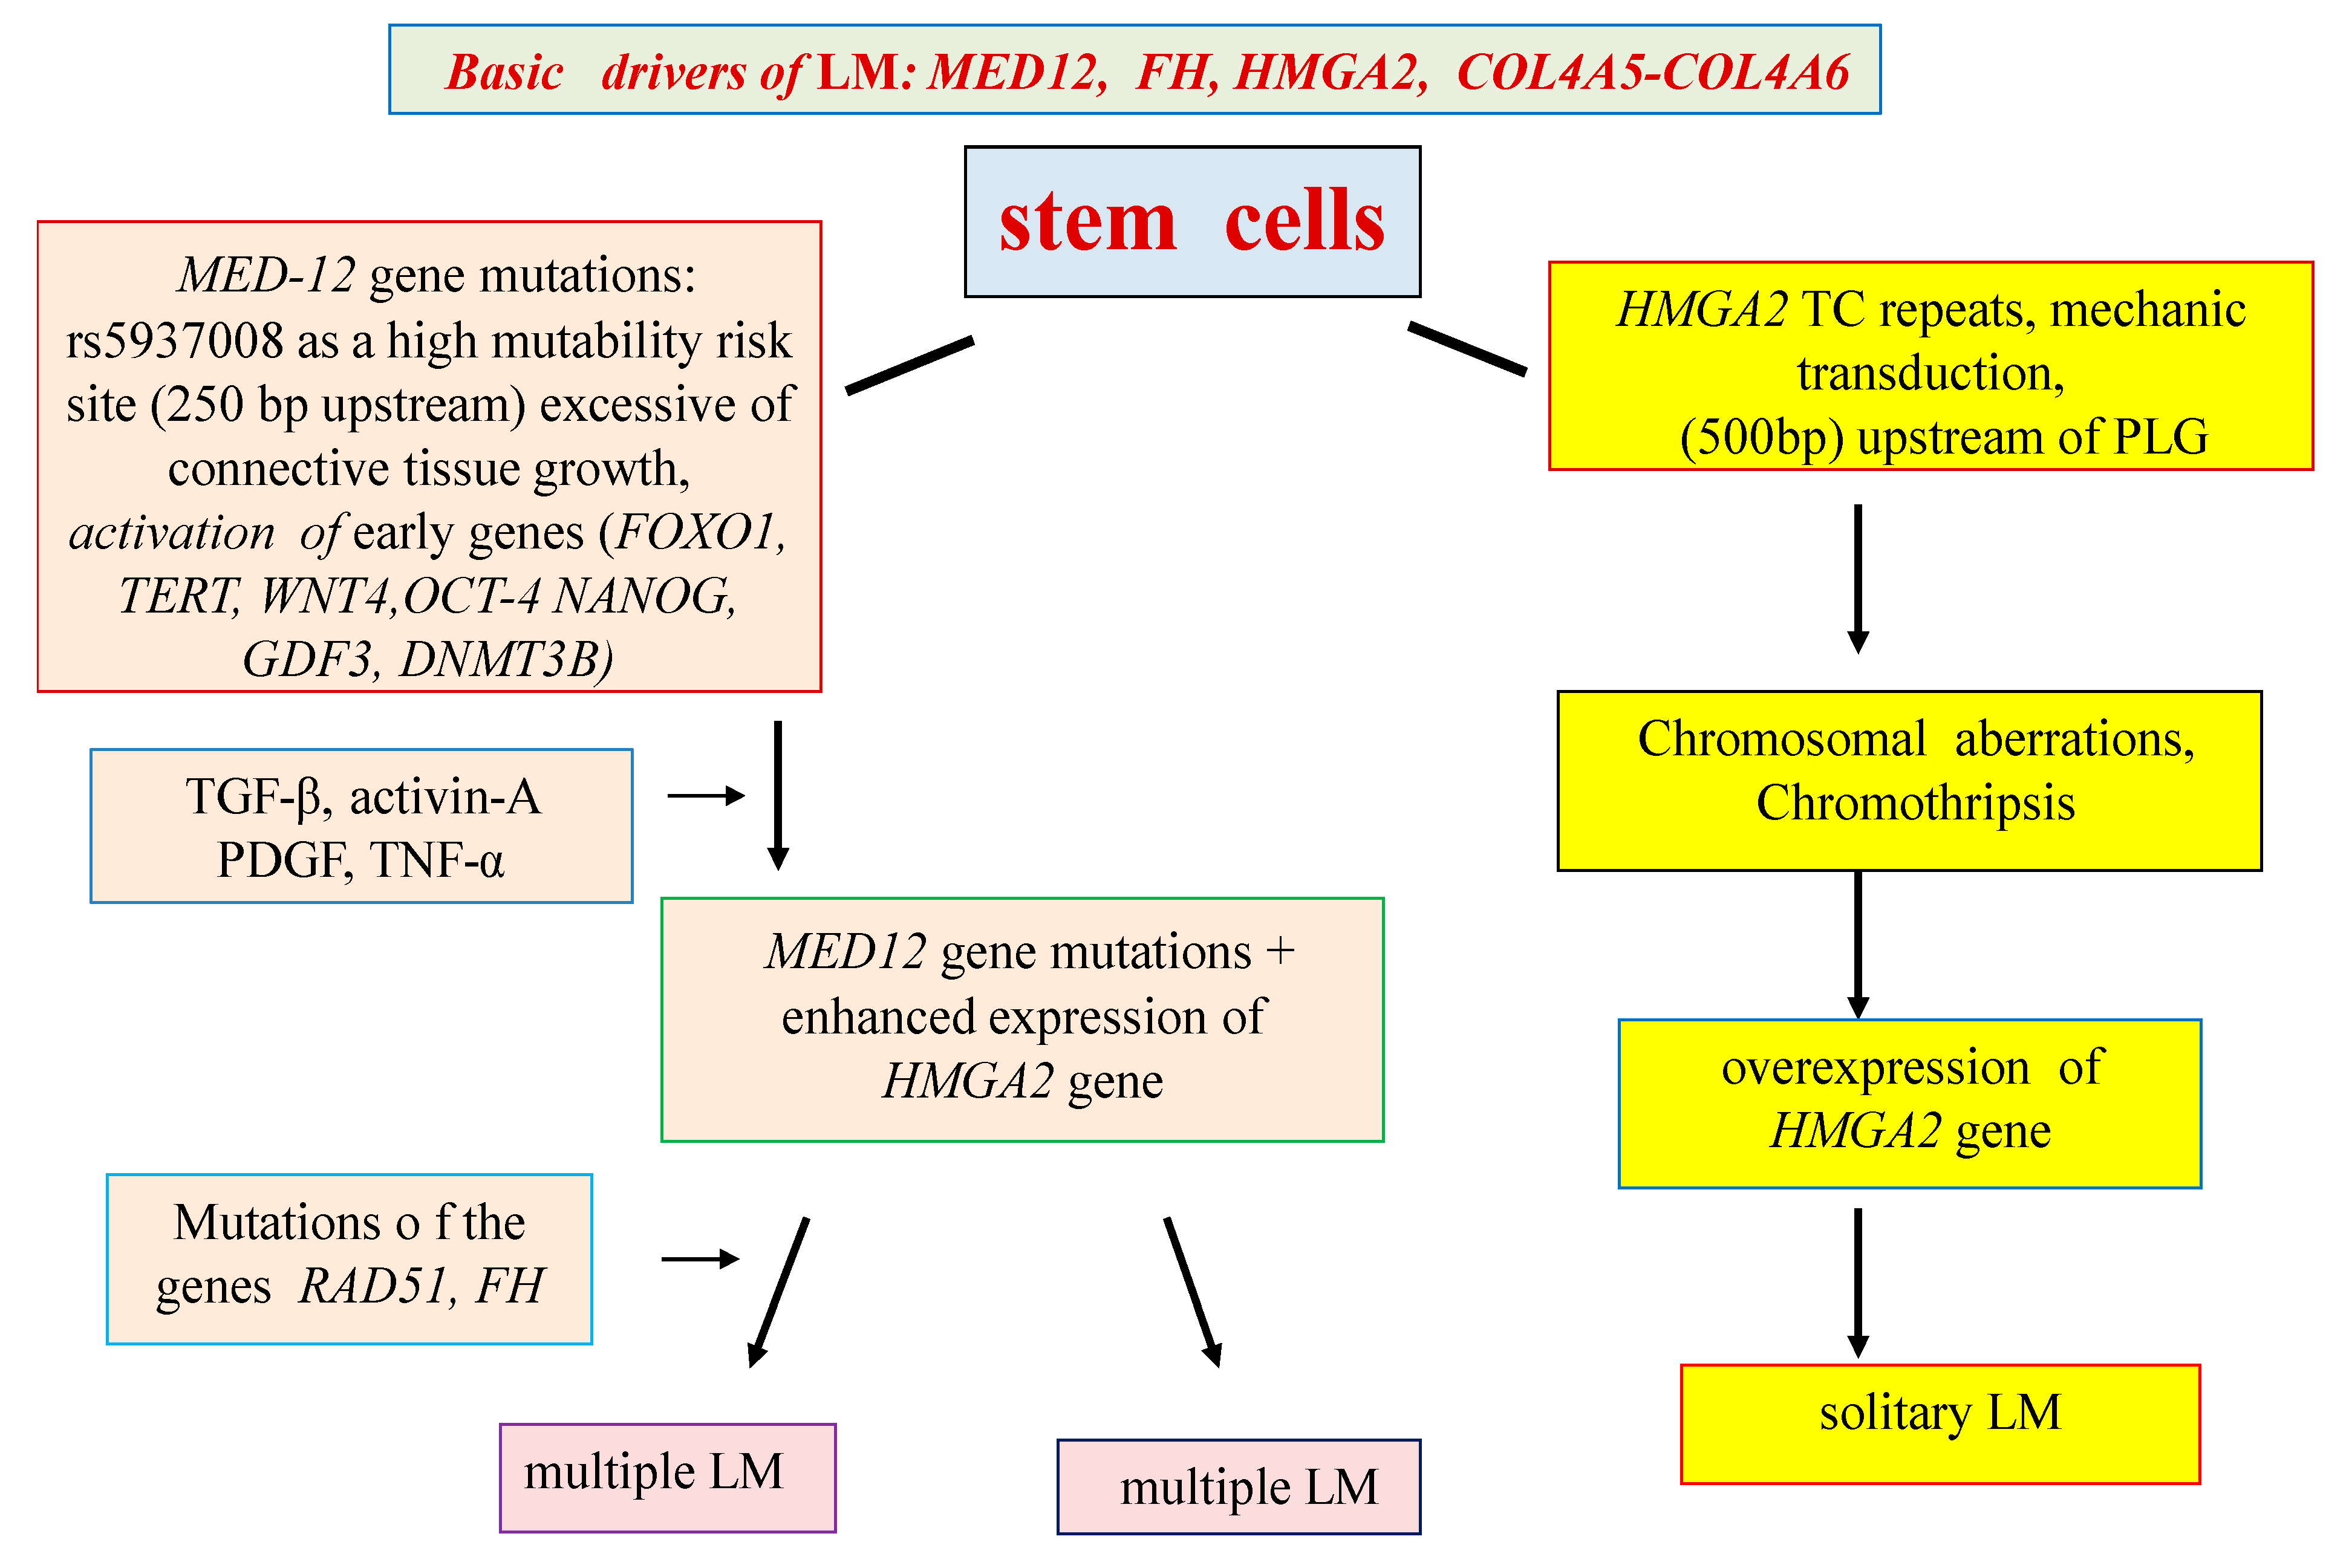

pathogenesis fig leiomyomas leiomyoma classification reproductive concepts procedural uterine surgical impact medical current management health figo

uterine fibroids pathogenesis leiomyomas calgary findings 2825 calgaryguide ucalgary

Uterine leiomyomas, current concepts: pathogenesis, impact on. Uterine leiomyoma at 10x magnification. Pathogenesis fig leiomyomas leiomyoma classification reproductive concepts procedural uterine surgical impact medical current management health figo